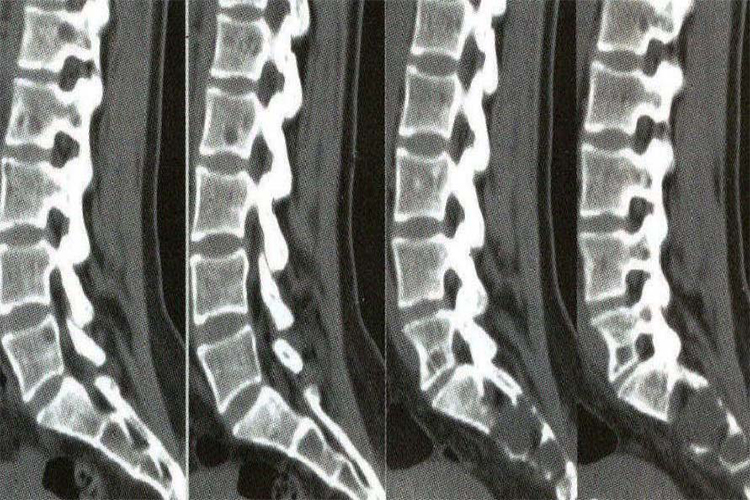

CT图像为断层图像

CT图像常规是横轴位断层图像,克服了普通X线检查各组织结构影像重叠的缺点,从而使各个器官组织结构得以清楚显示,提高了病灶的检出率。在CT扫描的基础上,利用计算机软件对CT轴位断面图像信息进行图像重组,可获得冠状位、矢状位二维图像以及三维立体的CT图像等,称为CT图像后处理技术。